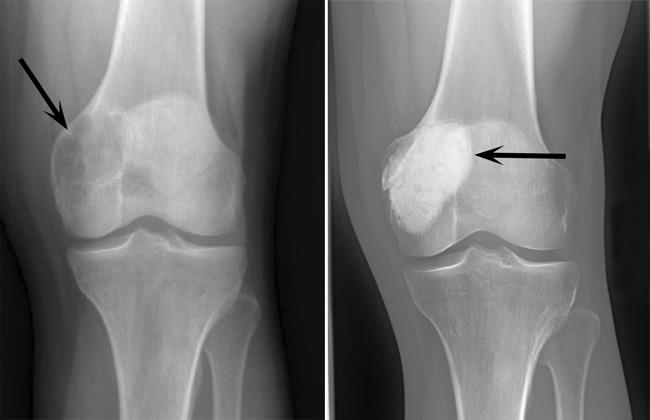

종양에 대한 세심한 이학적 검사 및 병력 청취가 이루어지고 단순 방사선 검사 및 MRI 등의 검사가 이루어질 수 있습니다. 단순 방사사선 검사에서 골단(관절 근처)에 한쪽으로 치우친 골파괴 양상의 소견이 나타납니다. MRI를 통해서는 병소의 범위 판정 및 연부조직 침범 유무등의 파악이 가능합니다.